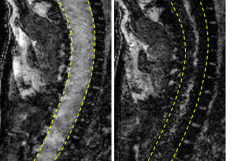

A l'occasion de la journée mondiale de la SEP organisée ce 31 mai, l’Institut du cerveau et de la moelle épinière (ICM, Paris) a présenté l’état de ses recherches dans ce domaine. Une des voies actuellement étudiées pour prévenir la progression du handicap est la réparation de la myéline. Plusieurs travaux ont ainsi mis en évidence l'importance de ce processus de "remyélinisation", ou régénération de la myéline, dans l'état de santé des malades. Dans sa forme la plus fréquente, la SEP se caractérise, en effet, par des poussées inflammatoires dans le système nerveux central, suivies de phases rémittentes, durant lesquelles la myéline se reconstitue en partie. De nouvelles techniques d'imagerie développées à l'Institut, plus précises que l'IRM, ont permis de montrer que ce potentiel de réparation est "très différent selon les patients", souligne Benedetta Bodini, neurologue chargée de recherche à l'ICM. Ainsi, en injectant un traceur spécifique, qui se fixe sur la myéline, avant de réaliser une tomographie par émission de positons (PET scan), "on peut mesurer à quel degré la myéline est atteinte", détaille-t-elle. En comparant les images cérébrales de différents patients, prises à trois mois d'intervalle, l'équipe de chercheurs s'est aussi aperçue que ceux qui avaient une bonne capacité de régénération de la myéline allaient mieux que les autres et présentaient moins de handicaps, ajoute-t-elle. "Cela veut dire que le jour où on aura des médicaments remyélinisants à notre disposition, on va pouvoir améliorer le pronostic des patients", espère le Dr Bodini.   Une molécule testée in vitro Première étape vers cet objectif, une autre équipe de l'ICM a identifié une molécule qui est secrétée de façon plus importante par les patients à faible capacité de remyélinisation. Cette molécule, baptisée CCL19, a fait l'objet d'un brevet début 2017. "C'est une cible thérapeutique intéressante: si on inhibe cette molécule, on pourra augmenter la réparation", a expliqué à l'AFP Violetta Zujovic, également chargée de recherche à l'ICM. Son équipe teste désormais, in vitro, pour le moment "différents anticorps" pour déterminer lequel sera à même d'empêcher l'action de la molécule CCL19 sans provoquer des effets secondaires majeurs. La SEP touche plus de deux millions de personnes dans le monde, dont plus de 100 000 en France et 400 000 en Europe.